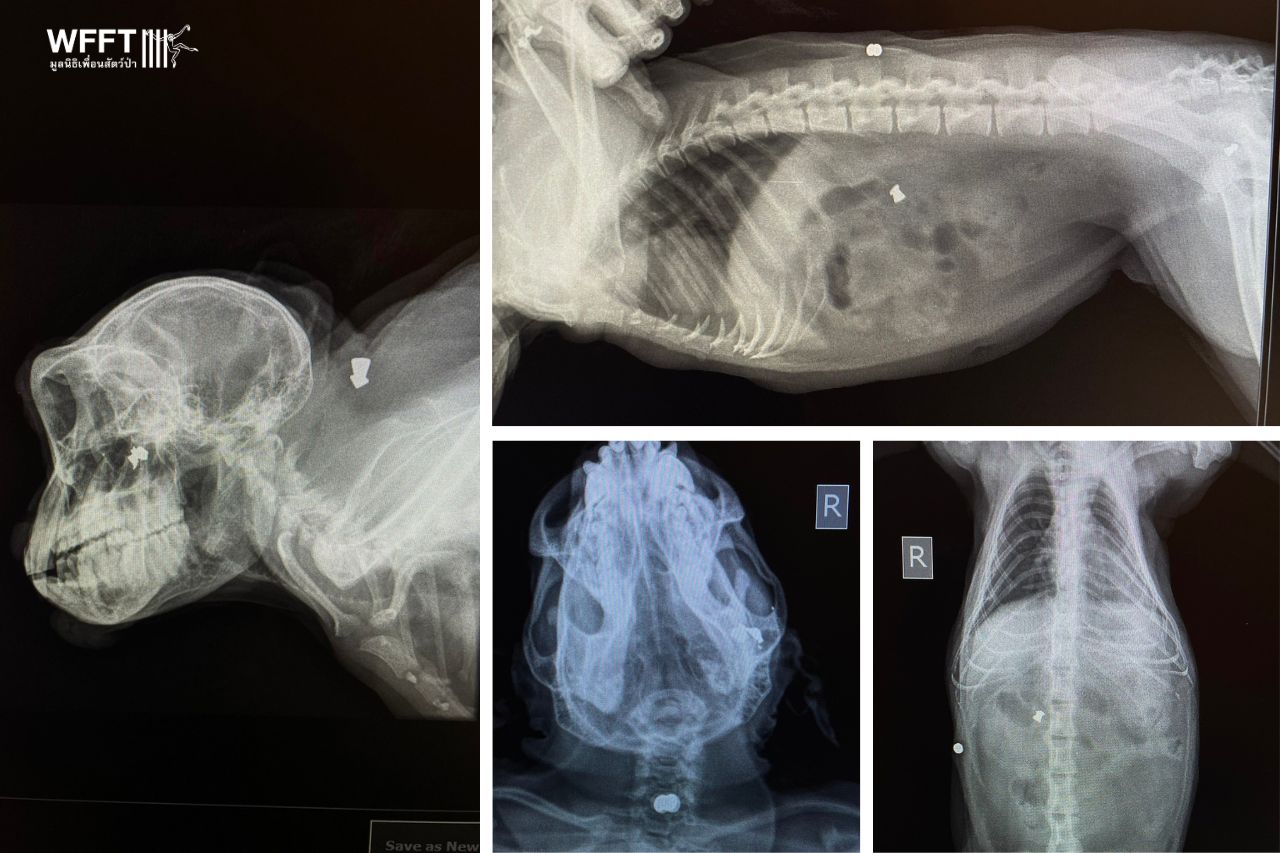

Wang, a wild long-tailed macaque from a local temple, was rescued by our team after reports of him falling off nearby house walls and appearing lethargic. However, a shocking discovery awaited us upon his arrival at the WFFT wildlife hospital: X-rays revealed his body was riddled with bullets.

While most of the bullets are old and the wounds healed, one has rendered Wang blind in his right eye. Fortunately, it did not penetrate his skull. Additionally, he has wounds on his lower lip and gums.